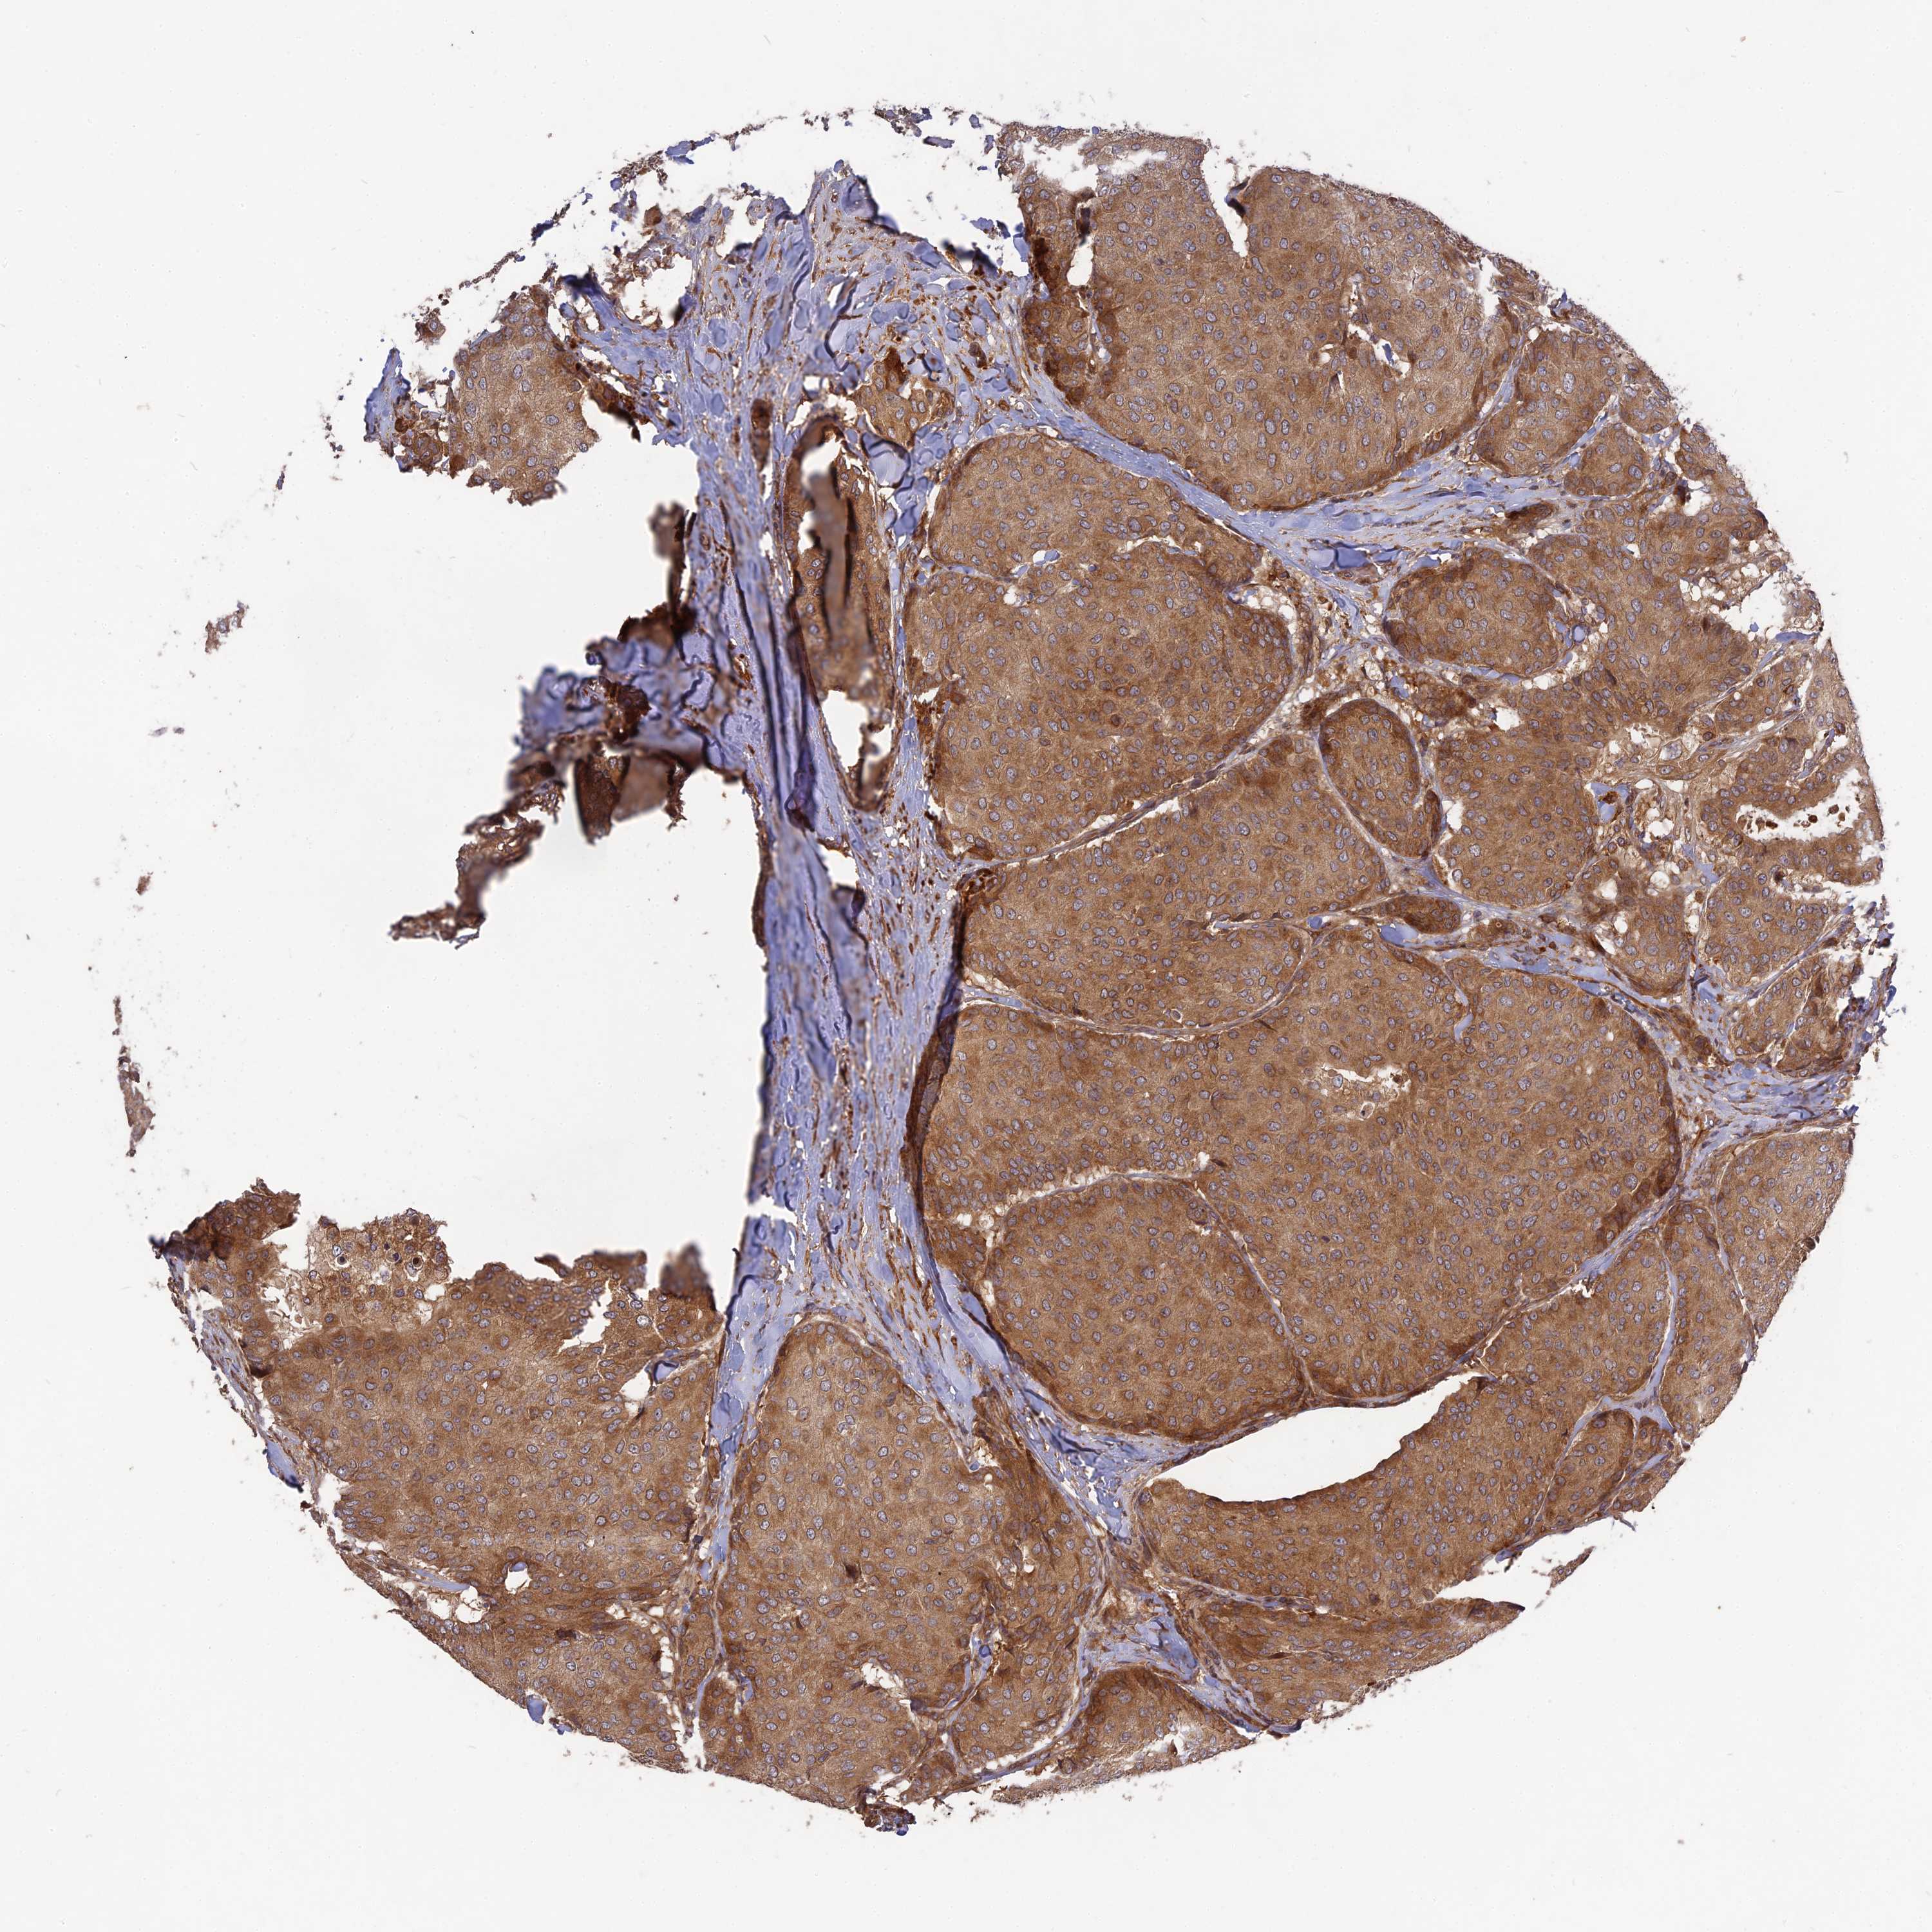

BRCA TCGA BRCA VALIDATION PROTEIN EXPRESSION

ANTIBODIES

AND

VALIDATION